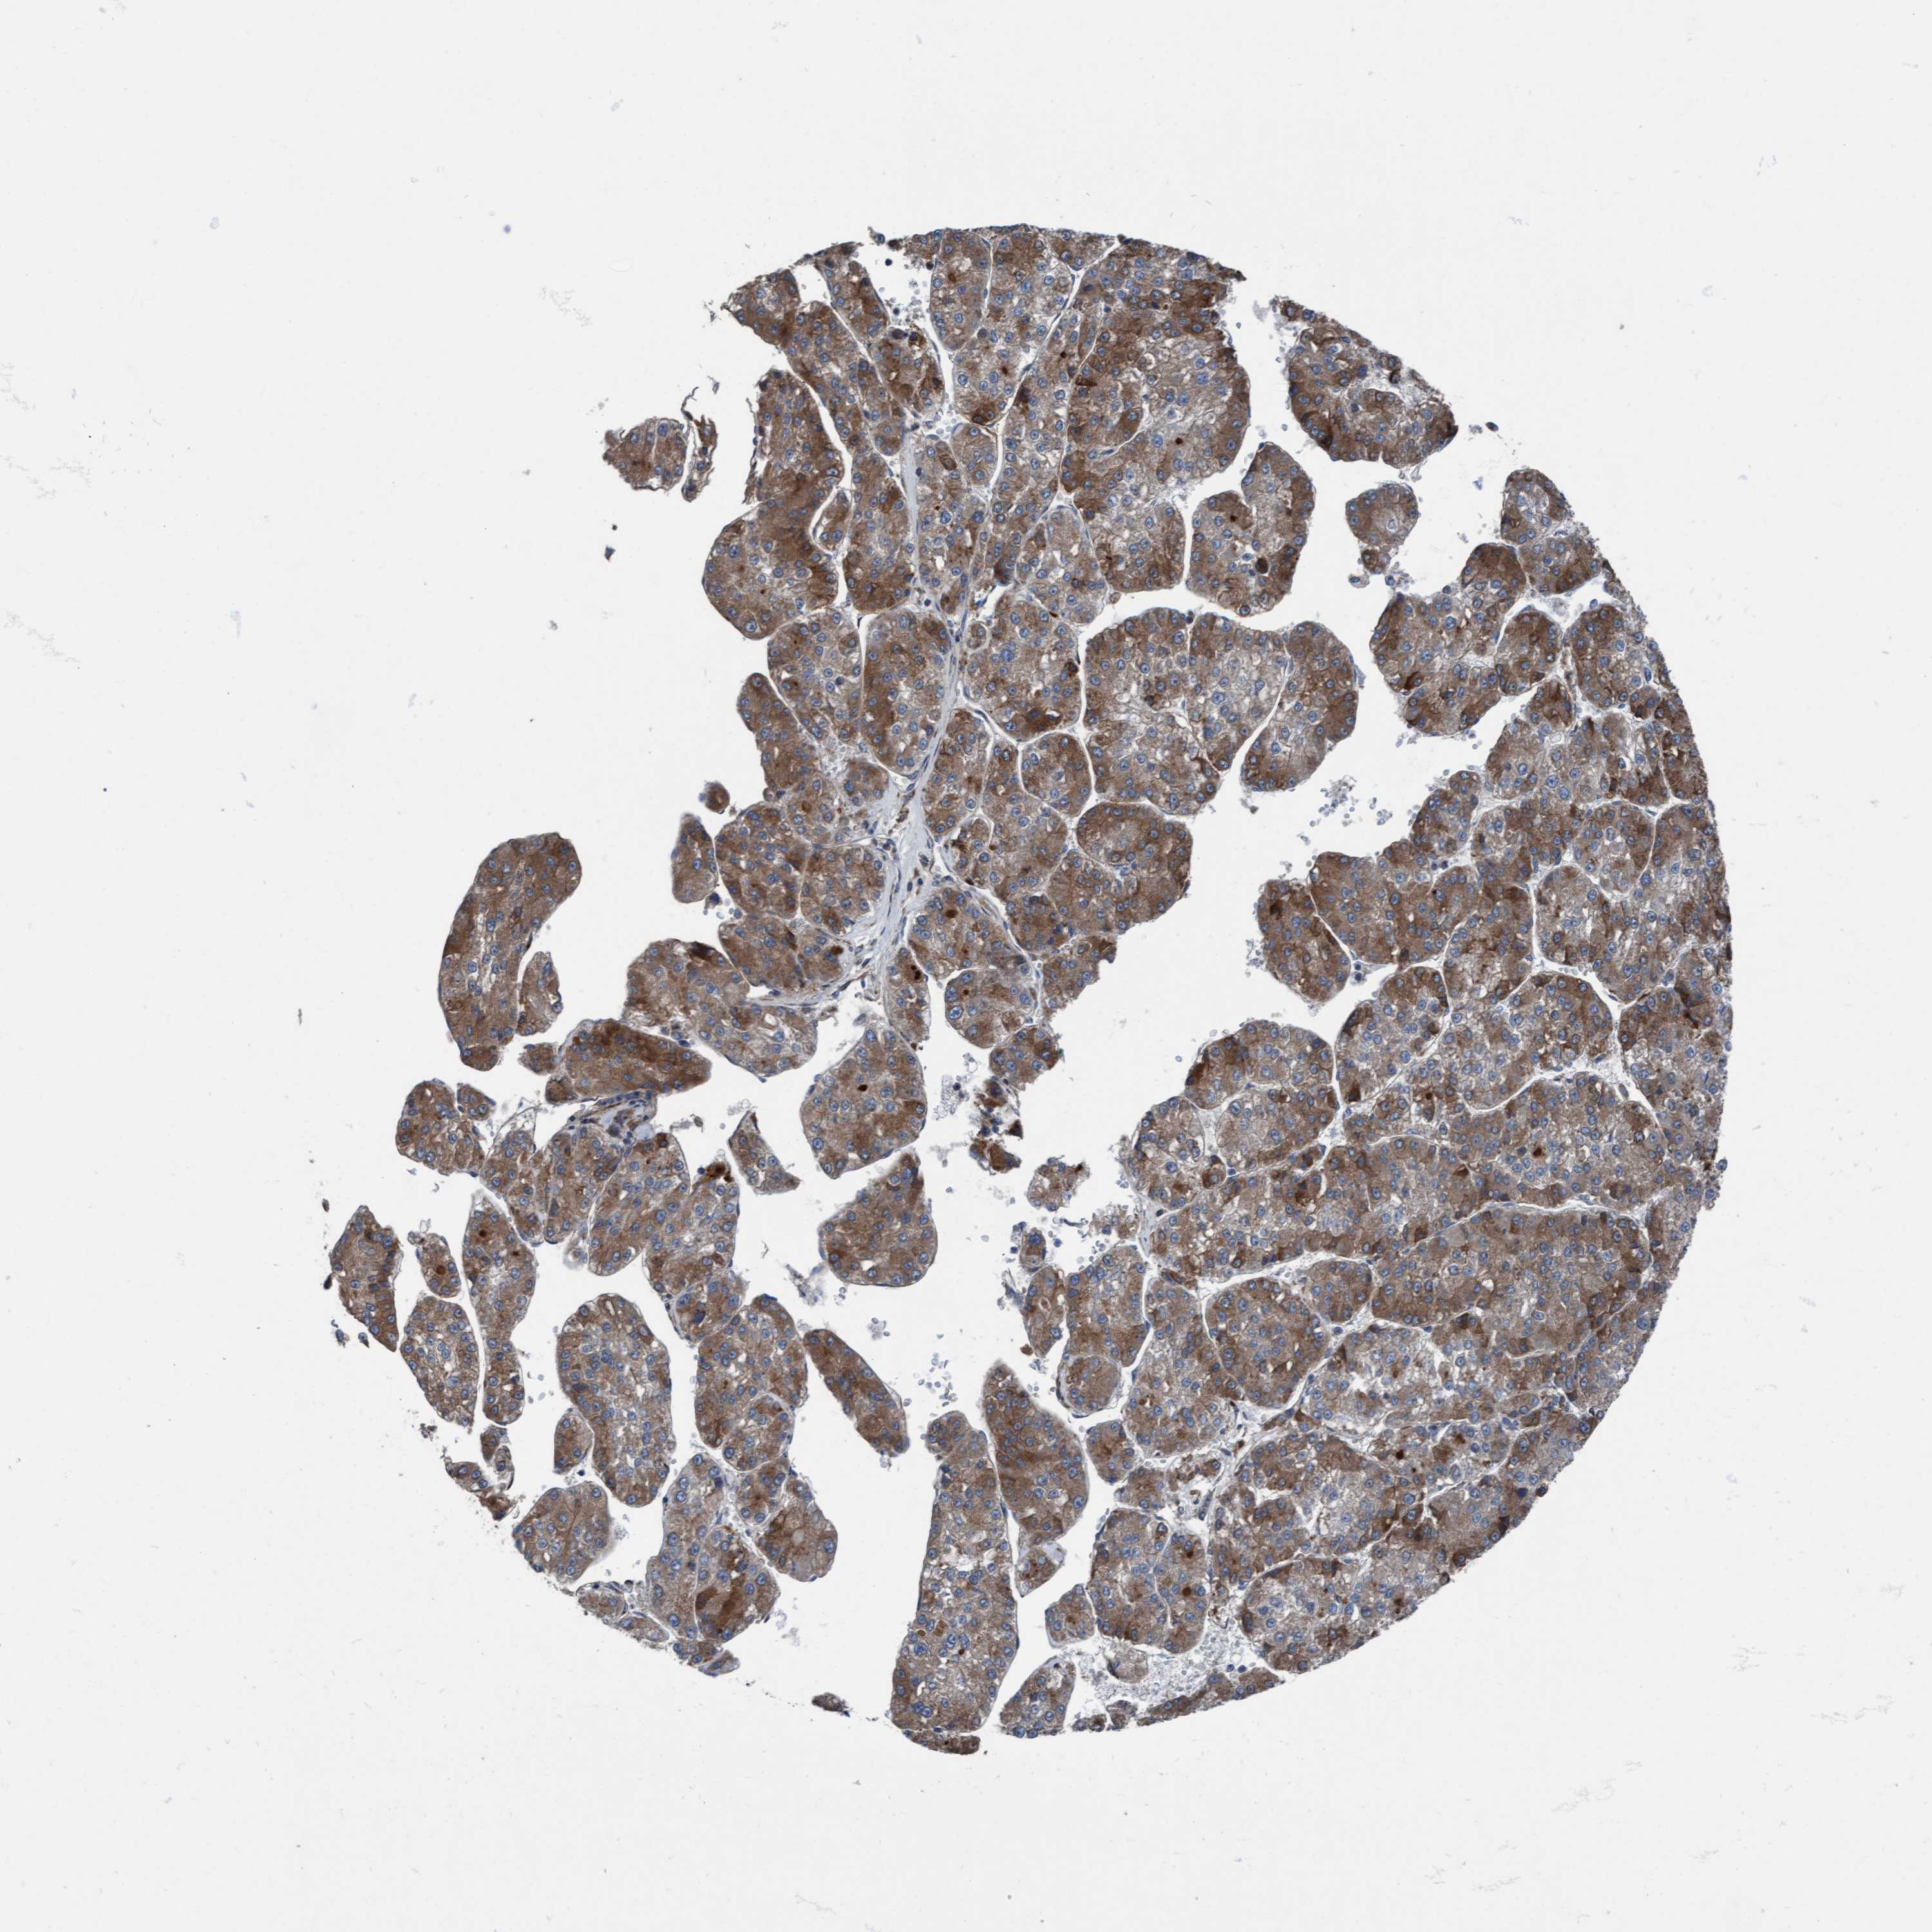

LIVER CANCER - Protein expressioni

A mouse-over function shows sample information and annotation data. Click on an image to view it in a full screen mode. Samples can be filtered based on level of antibody staining by selecting one or several of the following categories: high, medium, low and not detected. The assay and annotation is described here.

Note that samples used for immunohistochemistry by the Human Protein Atlas do not correspond to samples in the TCGA dataset.

Antibody stainingi

Antibody staining in the annotated cell types in the current human tissue is reported as not detected, low, medium, or high, based on conventional immunohistochemistry profiling in selected tissues. This score is based on the combination of the staining intensity and fraction of stained cells.

Each image is clickable and will lead to virtual microscopy that enables deeper exploration of all samples and also displays staining intensity scores, fraction scores and subcellular localization as well as patient and tissue information for each sample.

Antibody HPA023074

Staining

High

Medium

Low

Not detected

Intensity

Strong

Moderate

Weak

Negative

Quantity

>75%

75%-25%

<25%

None

Location

Nuclear

Cytoplasmic/membranous

Cytoplasmic/membranous,nuclear

Cholangiocarcinoma

Carcinoma, Hepatocellular, NOS